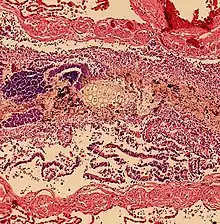

Histopathology of aspiration, taken from an autopsy, showing plant-like cells in a bronchiole. However, alveoli were clear, indicating a finding secondary to cardiopulmonary resuscitation rather than a primary cause of death.